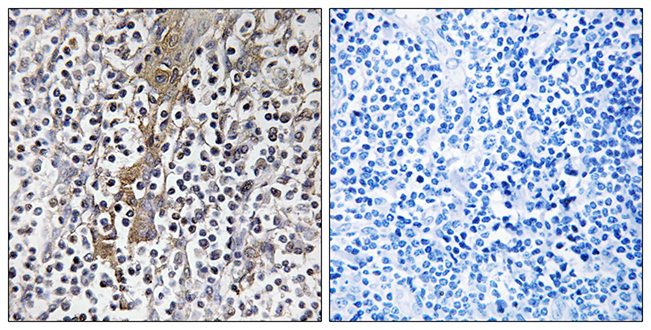

Anti-WASP AntibodyA97757

ApplicationsWestern Blot, ELISA, ImmunoHistoChemistry

ReactivityHuman, Mouse